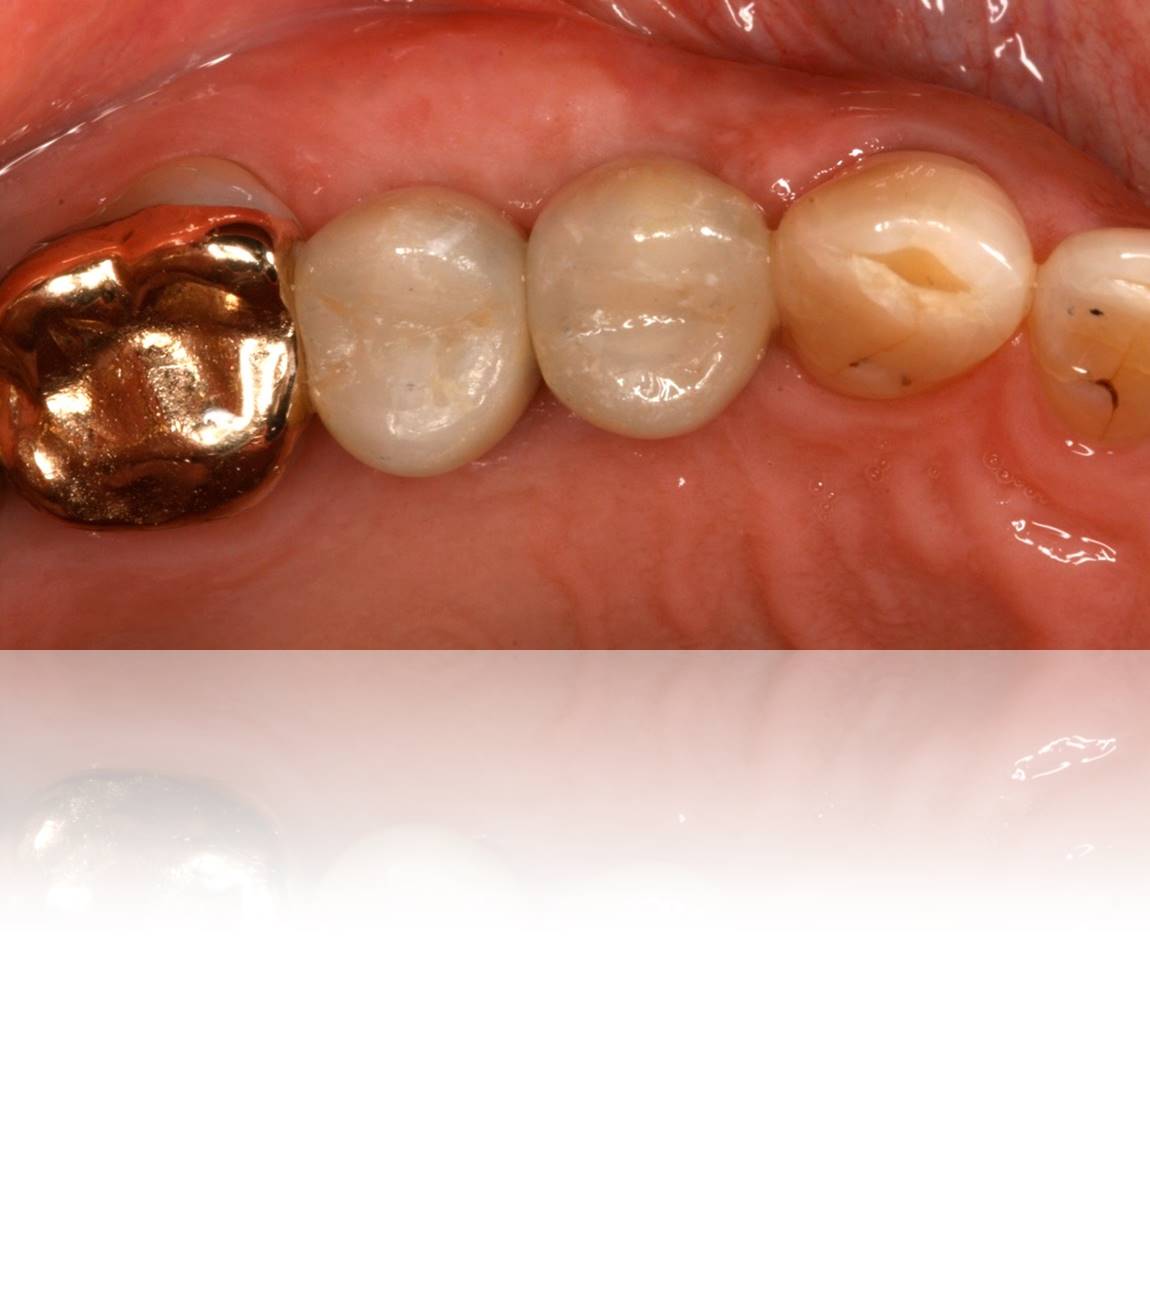

Figure 26. View of the “screwmentable” abutment/restorations in place in the mouth, prior to closing the access holes with composite.

Figure 26

Figure 27. The access holes were sealed with composite, masking any evidence of the underlying metal abutment and/or implant screw.

Figure 27

In its most simplistic form, the protocol for creating a “screwmentable” implant abutment/restoration involves the following sequence of steps: First, the correctly sized, predictable healing abutment (Figure 19 and Figure 20) is selected, and then an implant impression taken. The appropriate abutment (eg, prefabricated or custom) is then obtained (Figure 21). Gold-hue titanium and zirconia abutments produce less peri-implant soft-tissue color differences compared to the soft tissue around natural teeth than titanium or metal abutments.23 The clinician then works with the laboratory for the fabrication of the restoration, with the access holes occluded (Figure 22). Then, outside of the mouth, self-adhesive resin cement is used to connect the restoration to the abutment. Any excess cement must be thoroughly cleaned from the margin area with the unit outside of the mouth (Figure 23 and Figure 24). The abutment/restoration is screwed into place using either a screw wrench or torque wrench at the proper torque setting (Figure 25 and Figure 26), and, finally, the access hole is filled with composite (Figure 27 and Figure 28).